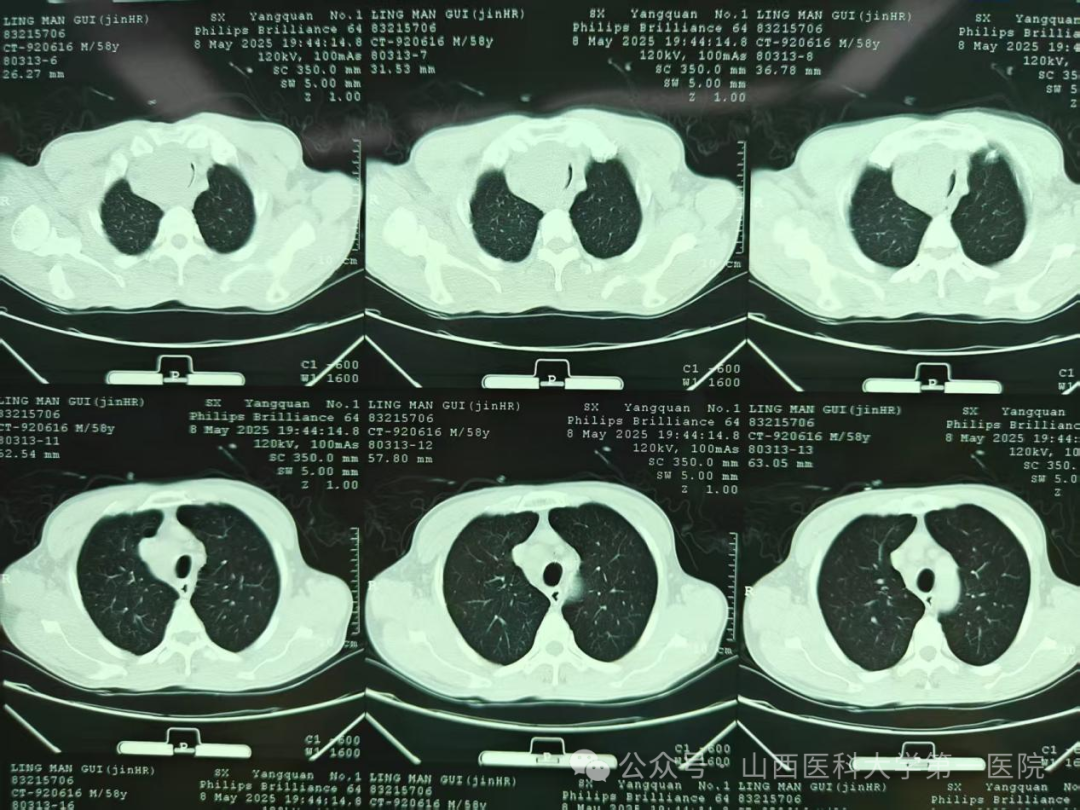

胸部CT提示大气道狭窄

5月9日,呼吸与危重症医学科郭志宏主任医师接到急诊会诊,一位58岁男性患者近两天出现进行加重的呼吸困难,只能端坐呼吸,无法平躺,同时伴有咳嗽咳痰,完善检查后考虑为右侧甲状腺区巨大新生物压迫气管。郭志宏主任医师与甲状腺外科董戬医生及麻醉科医生共同评估患者:该患者气管上段狭窄明显,气管插管不易通过狭窄部位,麻醉风险高,无法行全麻下外科手术解除气道梗阻,经过多学科讨论后决定立即行呼吸介入解除气道梗阻,择期手术治疗。

当日晚上9点,呼吸介入团队成员任寿安、郭志宏、尹建升、李艳青、王琛在手术室为患者在局部麻醉下行支气管镜检查,发现气管上段呈新月形外压性狭窄,管腔狭窄约95%,任寿安、郭志宏主任医师迅速置入气道支架,完全覆盖狭窄部位,麻醉科郭志佳副教授全程保驾护航。整个过程有惊无险,患者呼吸困难得到明显改善,平卧返回重症医学科密切观察。